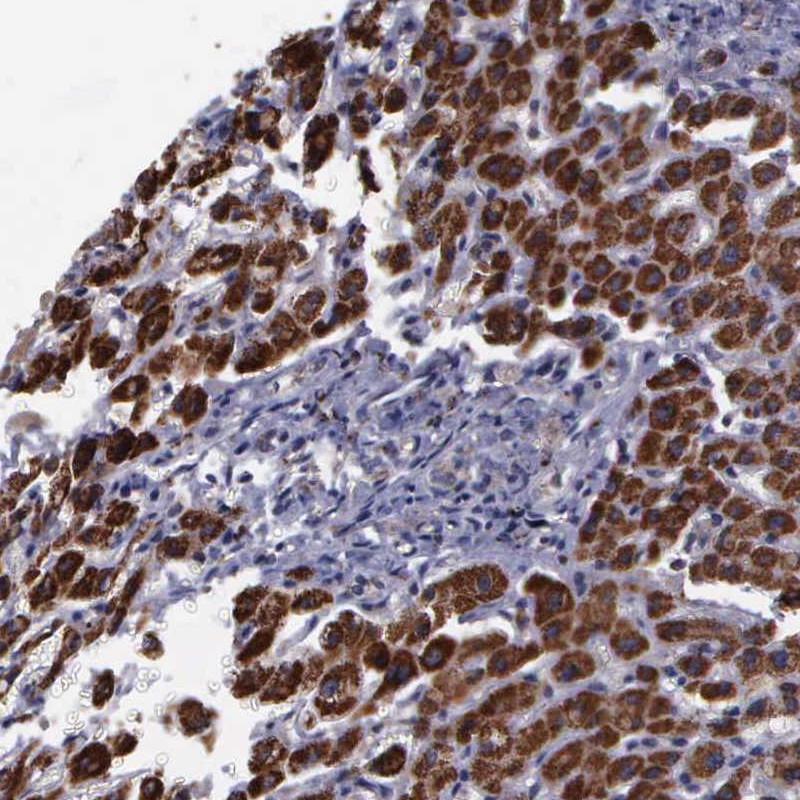

Immunohistochemical staining of human liver shows strong cytoplasmic positivity in hepatocytes.